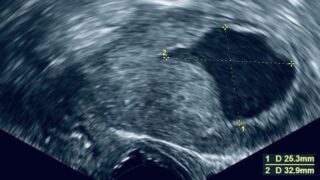

Triggering IVF Too Early May Reduce Egg and Embryo Potential - Fertility Plus